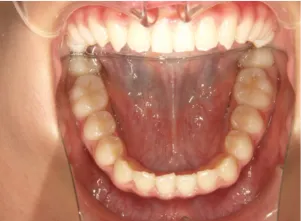

治療前①小2:8y1m 初診

治療中➁小3:9y8m QH、BH、前歯並び替え終了